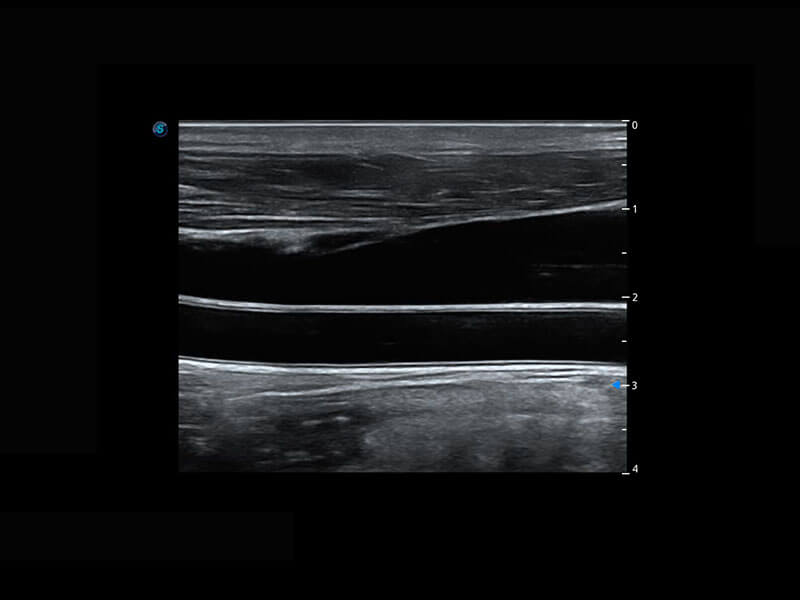

乳腺超声 / 新生儿

P60搭载宽频带线阵探头、宽景成像、弹性成像技术,为您提供乳腺应用方案。P60支持高频相控阵探头、线阵探头、腹部高频探头、腹部微凸探头等,丰富的探头群搭载敏感的彩色血流成像,适用于新生儿多种脏器检测要求,满足新生儿筛查需求。

• 新生儿肝血管癌

• 新生儿脊髓圆锥

• 新生儿心脏